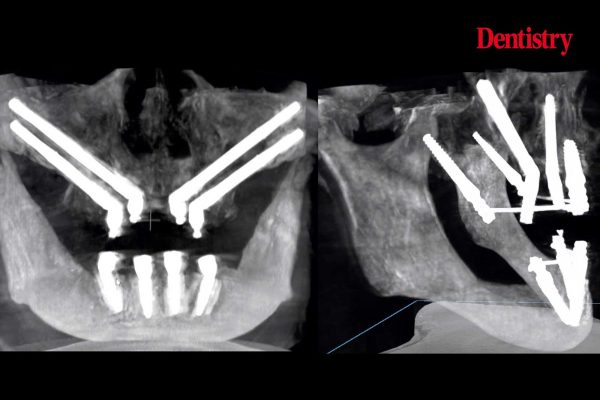

Digitally planned, immediate upper full-arch implant-supported restoration: case study

Usman Riaz reports on an immediate implant plan for a new dental referral patient with failing heavily restored dentition A…

Clinical Dentistry

Demystifying zygomatic implants in the atrophic maxilla

Vladimir Garcia Lozada explores the use of zygomatic implants, an efficient and predictable therapeutic option for rehabilitation of patients with…